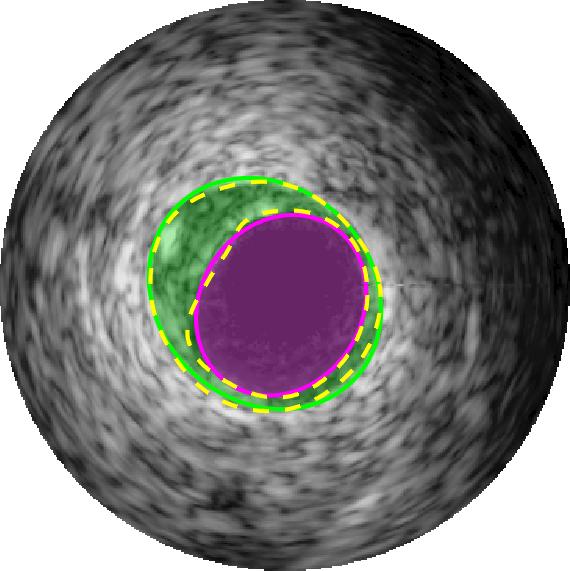

Qualitative evaluations are illustrated in Figure 4 and show the successful segmentation results of the proposed EREL selection strategy for 20 IVUS frames. The lumen areas are highlighted by the magenta colour while the media regions are green. Also, the manually annotated contours for both lumen and media are drawn as yellow dashed lines. As we can see, the chosen frames contain a variety of lumen and media morphologies.